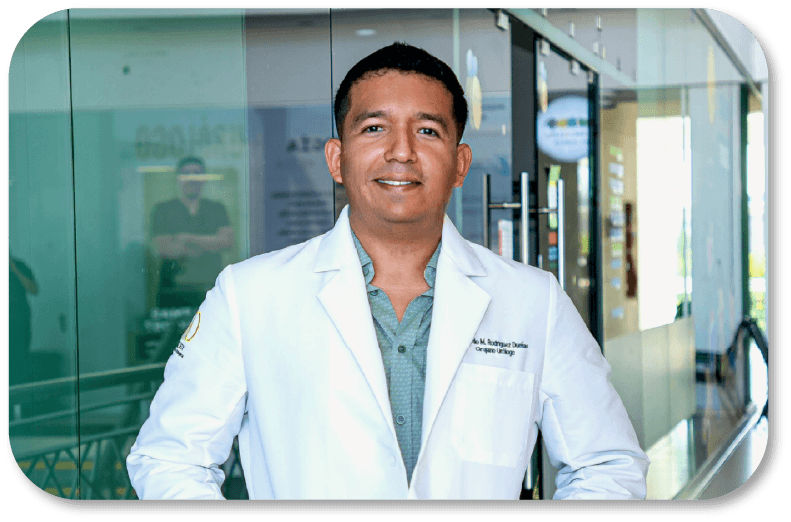

SOBRE MÍ

Dr. Eduardo Martín

Rodríguez Dueñas

CED. PROF. 12666613

Urólogo en Colima con gran experiencia en el campo de la urología.

Egresado de la Universidad de Guadalajara con especialidad en Hospital General Regional No.46 del Instituto Mexicano Del Seguro Social.

Certificado por el Consejo Nacional Mexicano de Urología y soy miembro activo de la Sociedad Mexicana de Urología

Sobre mi

Soy el Dr. Eduardo Martin Rodriguez Dueñas, urólogo con gran experiencia en el campo de la urología. Egresado de la Universidad de Guadalajara y realizando mi especialización en Hospital General Regional No.46 del Instituto Mexicano Del Seguro Social. Estoy certificado por el Consejo Nacional Mexicano de Urologia y soy miembro activo de la Sociedad Mexicana de Urologia

Mi objetivo es mejorar la calidad de vida de mis pacientes mediante diagnósticos precisos, tratamientos innovadores y una comunicación cercana. Me especializo en todas esas patologias que afectan la via urinaria, tanto en hombres como en mujeres, siempre priorizando un enfoque integral y empático con mis pacientes.